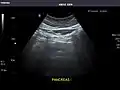

Pancreas

Pancreas: Visualized portions unremarkable.